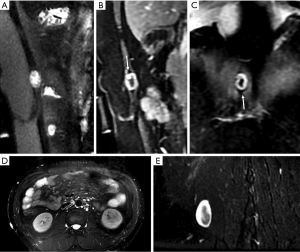

Metastases are the most common malignant lesions encountered in the anterior abdominal wall. The imaging characteristics of abdominal wall metastases are nonspecific, but they often resemble the known primary disease in other sites. The single most consistent discriminating feature is the rapid growth of lesions in a known cancer patient, who is usually at an advanced stage and has multiple other metastases. Metastasis of the umbilicus is known as Sister Mary Joseph’s nodule and typically originates from cancers of the gastrointestinal tract and ovary (52-54). The proposed metastasis route of Sister Mary Joseph’s nodule is along with the remnant structures at the umbilicus (55,56). Metastasis to the surgical wound or laparoscopic trocar site and needle-tract seeding after radiofrequency ablation also lead to the formation of abdominal wall metastases (Figure 10). These specific metastases may not be associated with widespread disease in contrast to hematogenous abdominal wall metastases.